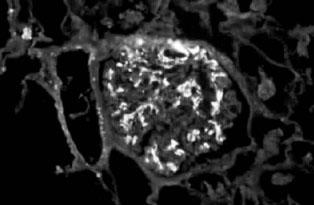

IgA肾病的典型病理表现为:在光镜下常见系膜细胞增生、基质增多(图2—10),常呈局灶节段性分布。IgA肾病轻微者则只有轻微系膜增生,亦可呈弥漫增生(常有局灶节段性加重)。约20%病例可出现新月体,通常不超过肾小球的30%。IgA肾病进行性病例可见球囊基底膜变形、裂解;肾小球基底膜“溶解”。免疫荧光镜下,可看见在肾小球系膜中呈弥漫分布的颗粒或团块状IgA沉积物(主要是IgA1(图2—11)。60%~90%的IgA肾病病例伴C3和IgG沉积,但强度较弱。IgA轻链以λ为主,有J链,无分泌块,通常无C1q和C3沉积。电镜下几乎都可见到细小均一的颗粒状电子致密物,分布于系膜区;若在上皮下或内皮下出现,则可判断为IgA肾病病情严重。上皮细胞足突则常常是正常的。

图2—11 IgA肾病,IgA呈团块状沉积于系膜区(免疫荧光 x400)